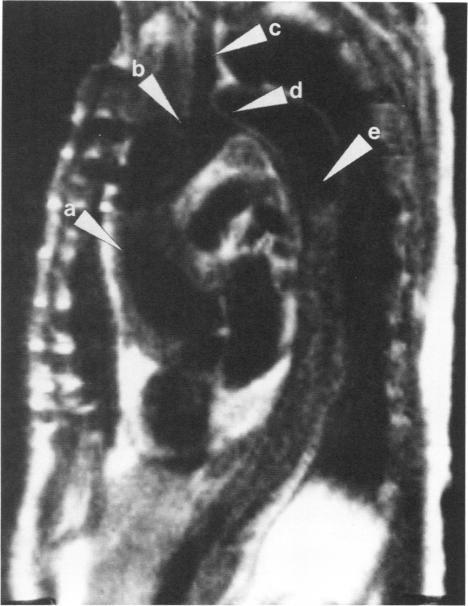

Magnetic resonance imaging is an excellent noninvasive method for evaluating thoracic aortic dissections. A variety of magnetic resonance scans of aortic dissections are shown, documenting the ability of magnetic resonance to image the true lumen, the false channel, and the intimal septum. Detail is provided on magnetic resonance imaging techniques and findings.

磁共振成像是评估胸主动脉夹层的一种出色的非侵入性方法。展示了各种主动脉夹层的磁共振扫描图像,证明了磁共振对真腔、假腔和内膜隔膜成像的能力。文中提供了磁共振成像技术及结果的详细信息。